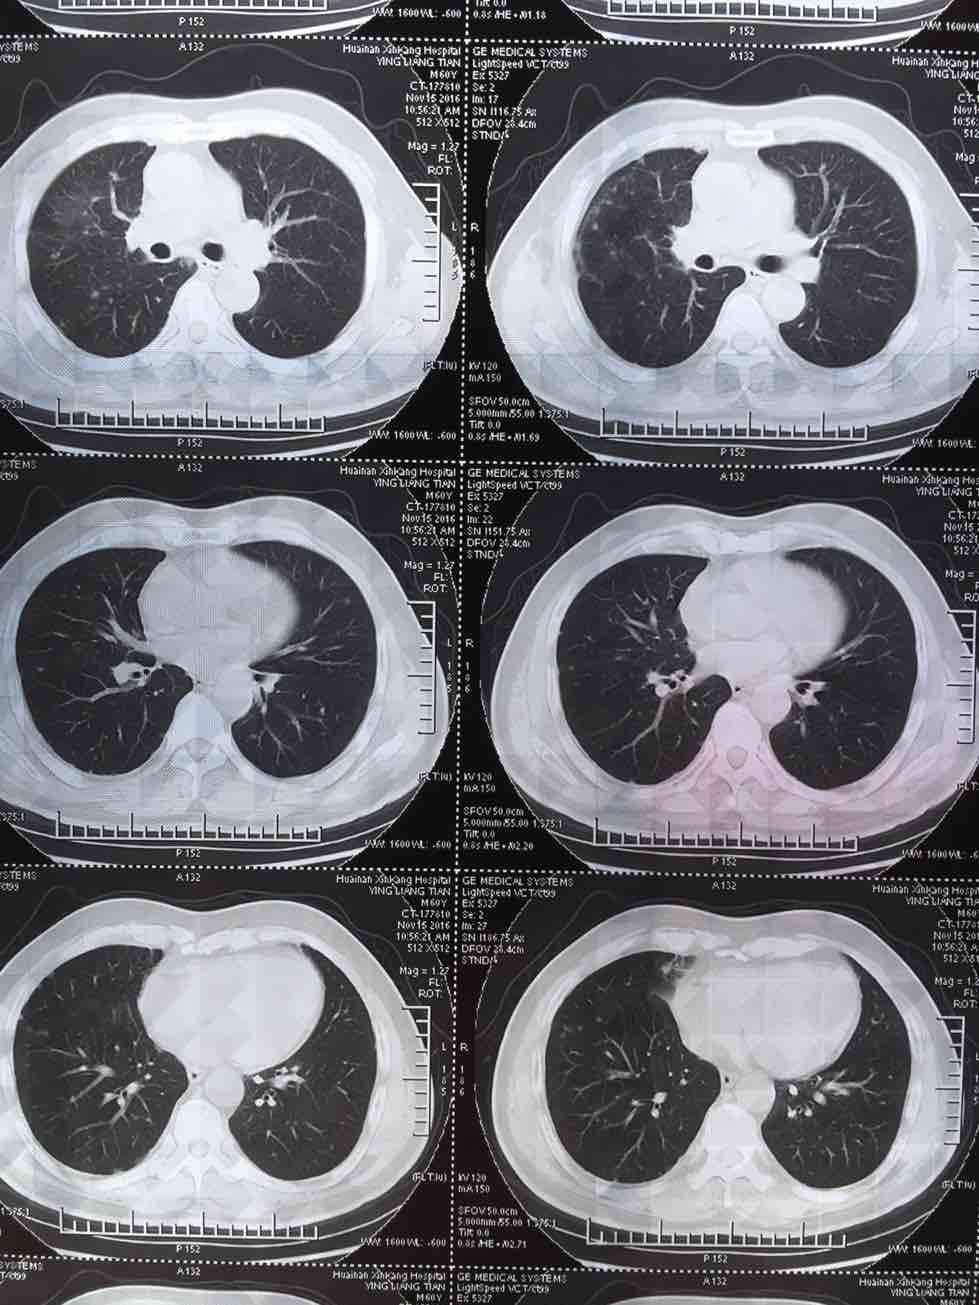

肺腺癌晚期治疗经验

我父亲今年一月份查出肺腺癌晚期伴两肺及腰椎骨盆转移,吉西他滨 顺铂两次,无效,后培美曲塞用了六次,最后一次今年7月25号出院,控制很好,期间主病兆放疗15次有所缩小,今年10月15号复查,两肺转移兆增多增大,紧接着做穿刺基因检测,结果野生型,顿时绝望,盲吃易瑞莎一个月,老天爷眷顾有效,病兆明显缩小或消失!!